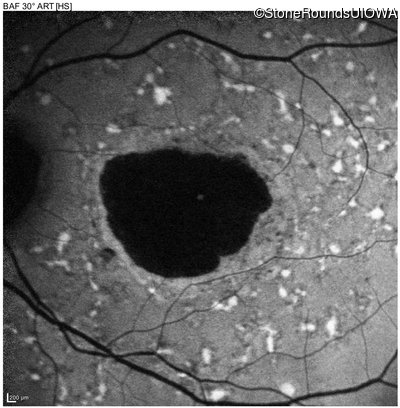

AR Stargardt Disease (IIA)

Age at visit: 52 years

This 52 year old man first noticed reduced visual acuity at age 21.

Diagnosis & molecular findings

AR Stargardt Disease ABCA4 Glu471Lys GAA>AAA / Glu2131Lys GAA>AAA Asp2181 del36gaCCTGAACCCTGTGGAGCAGTTCTTCCAGGGGAACTT AR